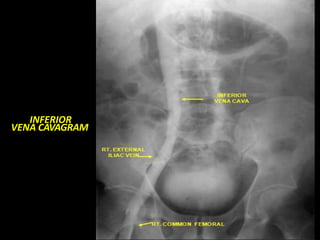

INFERIOR

VENA CAVAGRAM